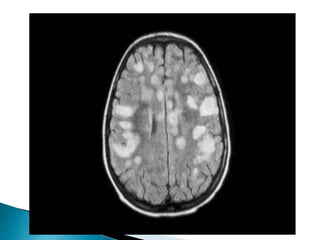

 Polman et al. reviewed McDonald’s diagnostic

criteria in 2010 and proposed the following :

 Space: One or more lesions with and without

gadolinium enhancement in two of the

following areas:

 periventricular,

 juxtacortical,

 infratentorial, or

 spinal cord.

 Time: One new lesion on T2 sequences or a

gadolinium enhancing lesion when compared

to the previous MR image, and concomitant

finding of asymptomatic lesions with or

without enhancement.

 On the sagittal plane, the plaques may be anterior,

central or posterior.

 Acute lesions enhance with gadolinium, due to

rupture of the blood-brain barrier. This enhancement

is less in cerebral lesions.